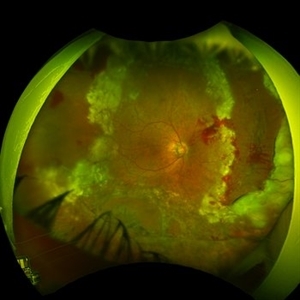

Ultra wide-field fundus photograph of a 55-year-old gentleman who is 4 days after surgery with scleral buckling, pars plana vitrectomy, perfluoron tamponade, membrane peeling, direct fluid-PFO-oil exchange, nasal and temporal retinectomies, and endolaser photocoagulation. Visual acuity was 20/150 under oil.

Photographer: Megan McLandsborough, Lakeland Eye Clinic

Imaging device: Optos California UWF Camera

Condition/keywords: endolaser, Membrane Peel, PPV, proliferative retinopathy, proliferative vitreoretinopathy (PVR), Retinal Detachment, retinal detachment with retinal defect, scleral buckle, submacular perfluorocarbon liquid (PFO)